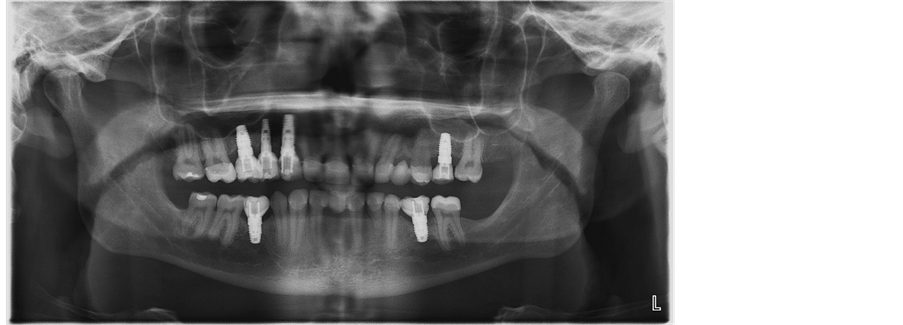

Deficient posterior maxillary alveolar bone height can complicate surgical place- ment of dental implants. When the PMABH deficiency is 1 - 3 mm, the common treatment modalities utilized are the indirect sinus lift or the use of short implants. Due to institutional restrictions on implant brand, dental implants that are shorter than 8 mm are not used at our facility. Because of this, the options available were to perform a direct sinus lift, an indirect sinus lift or place implants without a sinus lift where the apical 1 - 3 mm of the implant protrudes into the maxillary sinus. We utilized the last option where the maxillary sinus floor was perforated to engage the cortical bone to place the implant (Figure 1 & Figure 2). We observed a success rate of 100% in our patient population. Nooh et al. reported on a series of 56 patients who received 63 implants [4] , where only

Figure 1. Postoperative (stage 2) Panoramic radiograph of Left maxillary first molar implant placed with sinus floor perforation and 2 mm of apical implant protruding into Left maxillary sinus.

Figure 2. Panoramic radiograph of the same patient in Figure 1 nine months after prosthetic restoration.